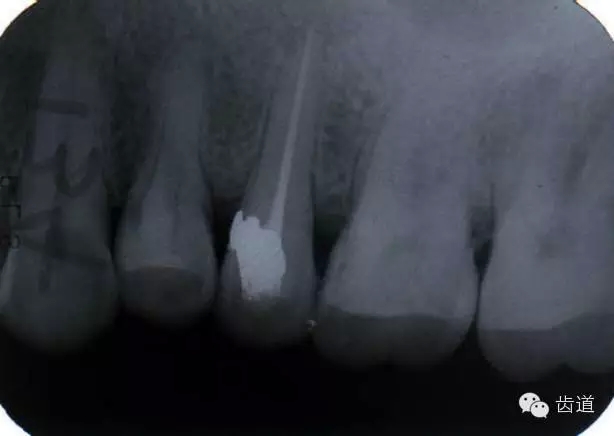

左上7近中頰根器械折斷

右上6腭根器械折斷